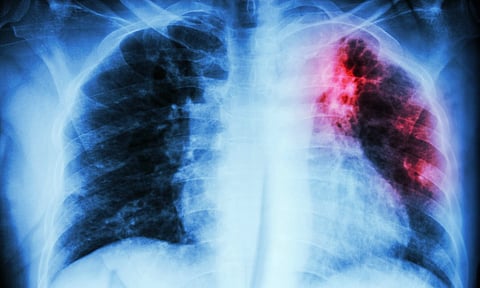

After two challenging years of the pandemic, India has seen a reduction in tuberculosis (TB) incidence by 16 per cent, almost double the pace witnessed globally, Union Health Minister Mansukh Mandaviya said on Tuesday.

"After two challenging years dominated by disruptions caused by the COVID-19 pandemic, globally we saw a reduction in TB incidence by 8.7 per cent, while in India, we were able to demonstrate a reduction of 16 per cent, almost double the pace," he said.